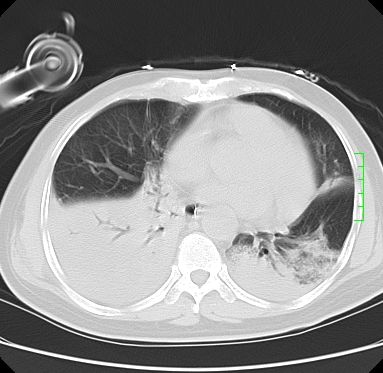

icu病人,几天都没明确诊断。m,76y,咳嗽、咳痰1周,伴气促,右胸痛入院,pe:t38.3c p135 r25 bp135/85。双肺可闻及大量湿罗音,心、腹未见明显异常。诊断:1心衰?2肺部感染?3冠心病?

9号平片

11号ct

双肺感染性病变,下叶膨胀不全,胸水,左室大。

1)两肺感染性病变(右肺下叶肺脓肿可能)。2)双侧胸腔积液,以右侧为甚。

ards,肺感染性病变,右下叶实变,双侧胸腔积液,右侧为著,叶间胸膜积液,右上肺陈旧性tb纤维灶,左室大。